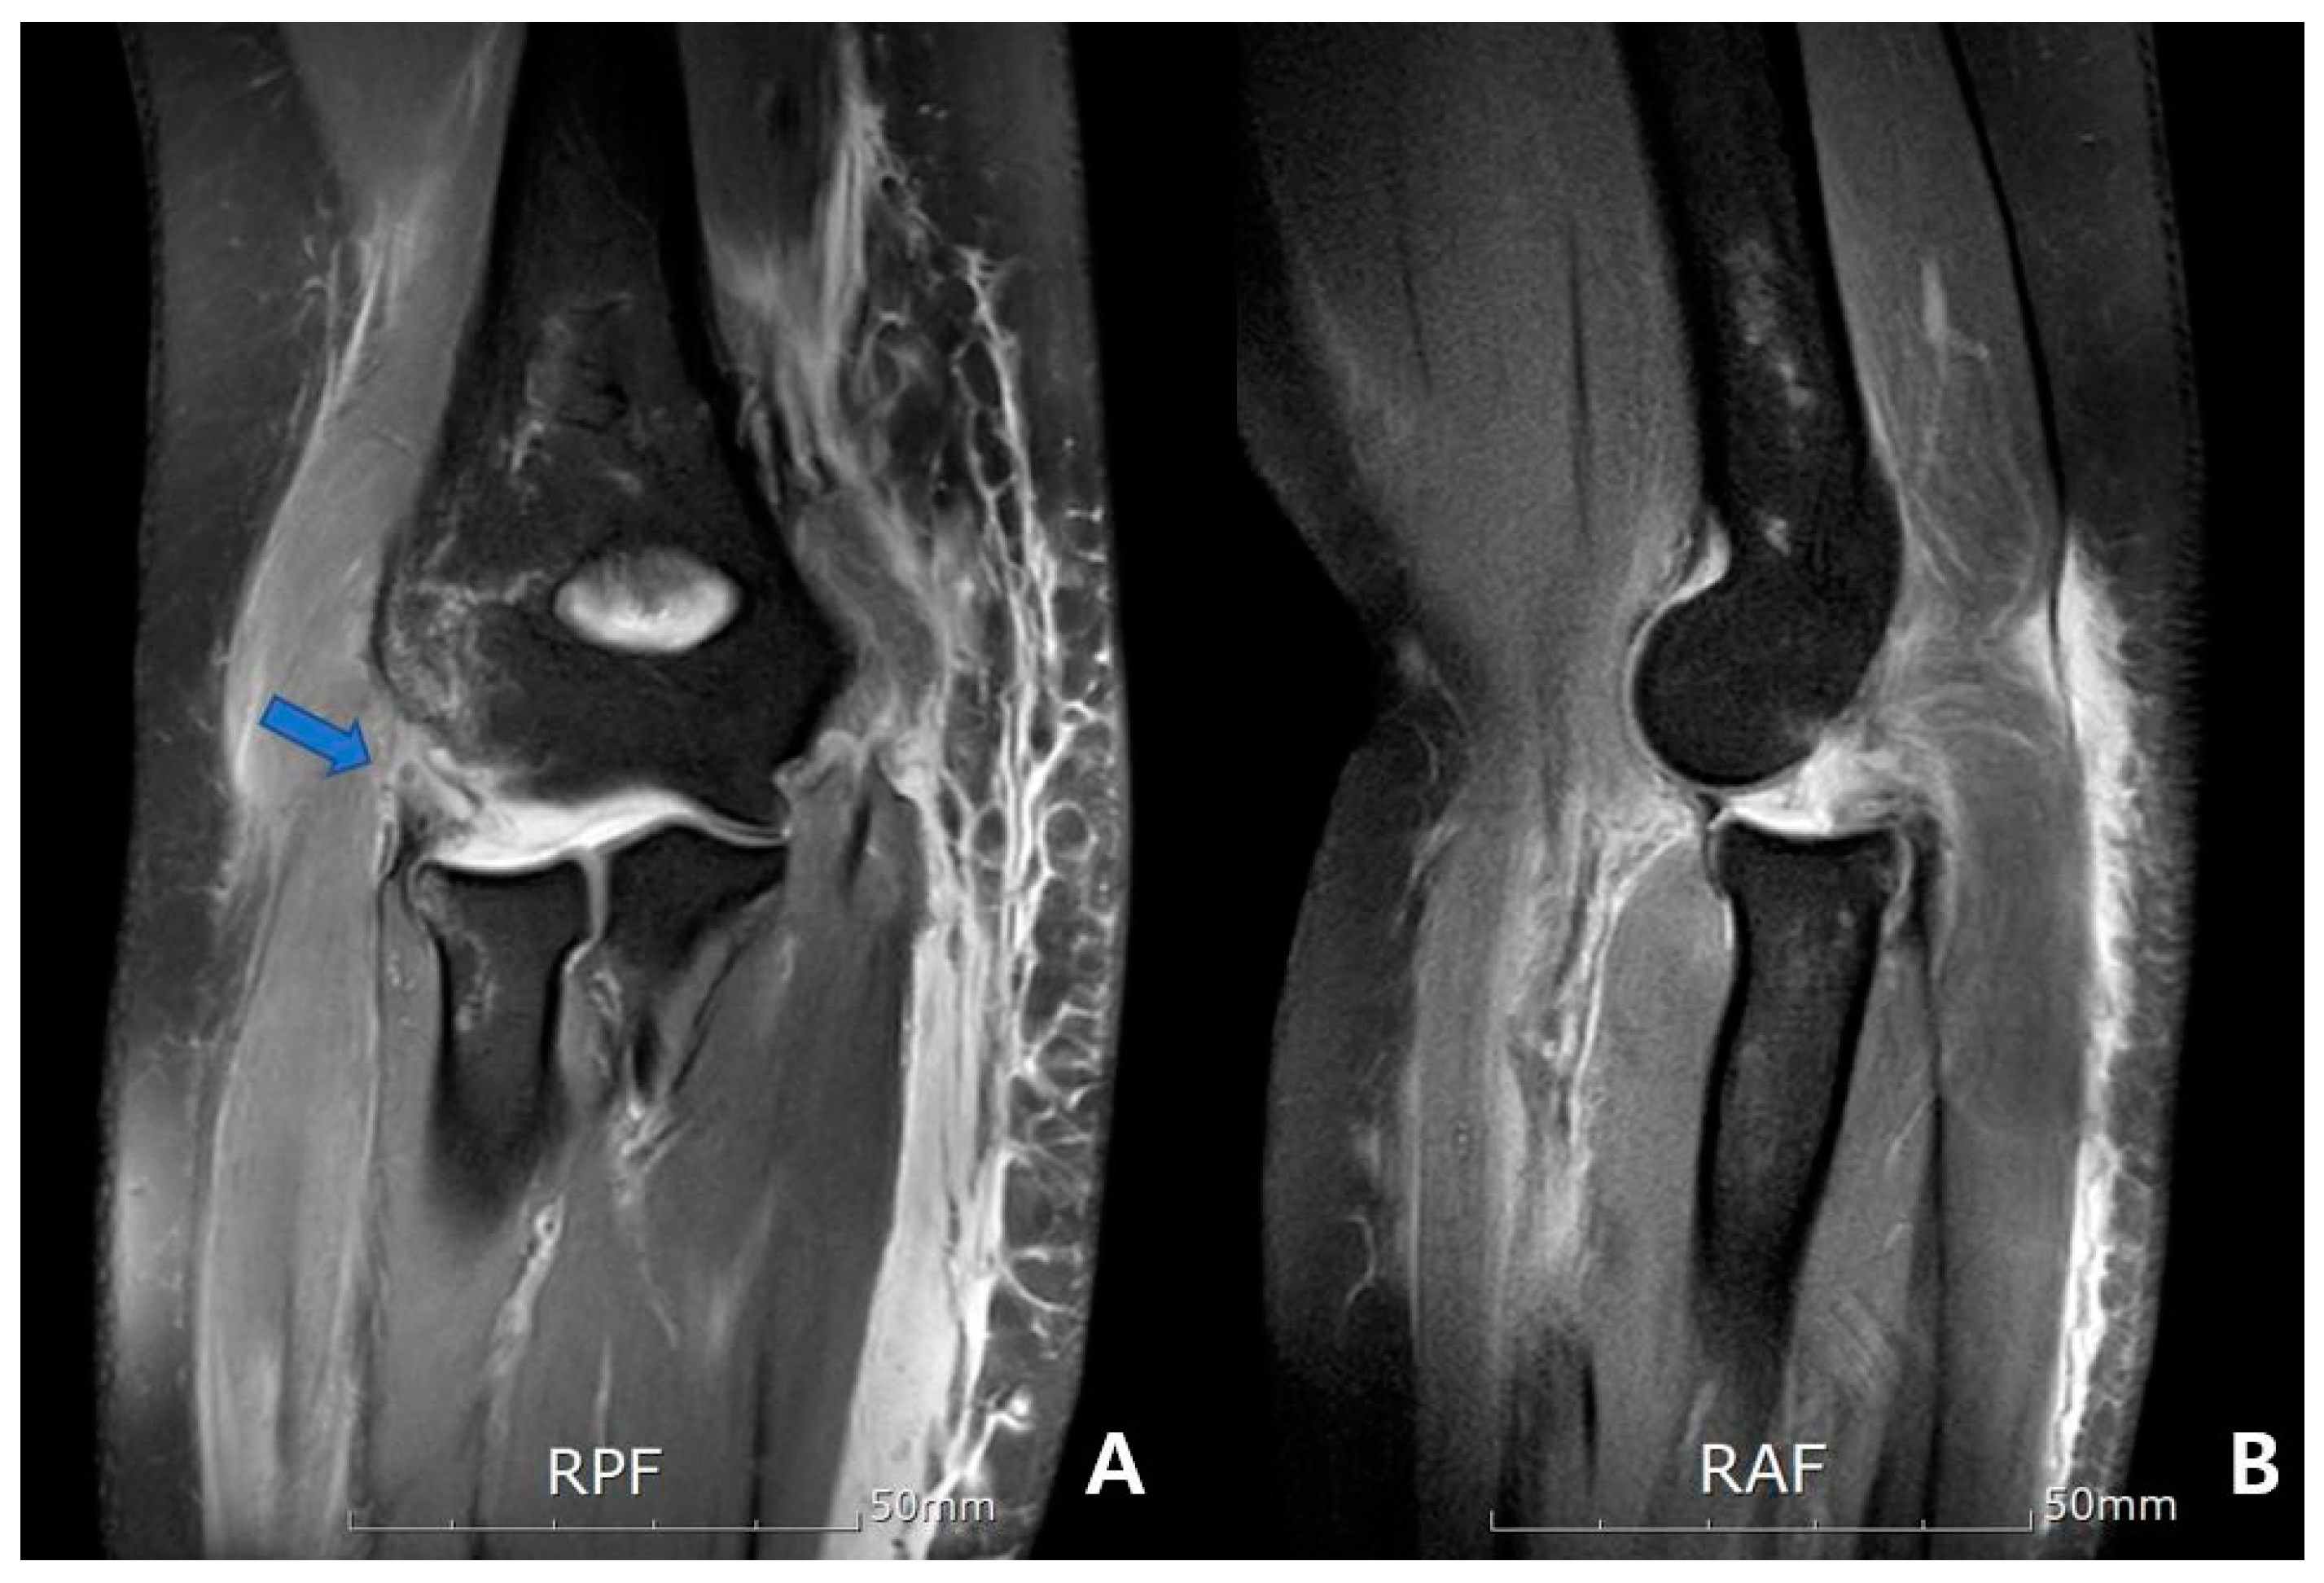

| Common extensor complex | 0.028 * | ||

| Intact | 0 (0%) | 0 (0%) | |

| Partial tear | 4 (26.7%) | 11 (73.3%) | |

| Complete tear | 11 (73.3%) | 4 (26.7%) | |